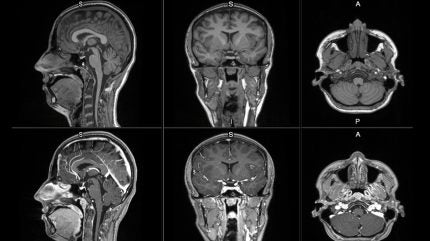

The new contrast agent is intended to improve MRI detection and visualisation of lesions with abnormal vascularity in the central nervous system and body.

MRI contrast agents help enhance the visibility of abnormal structures during scans, supporting improved differentiation between healthy and unhealthy tissue.

Early clinical images of mangaciclanol indicate comparable relaxivity to gadobutrol, a widely used gadolinium-based agent, with similar diagnostic potential.